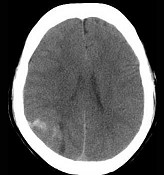

[单选题]男,37岁,头痛、头晕1年余,加重3天,CT检查如图所示,最可能的诊断为()A .脑出血B .脑血管畸形并出血C .脑膜瘤并出血D .颅内动脉瘤E .转移瘤并出血